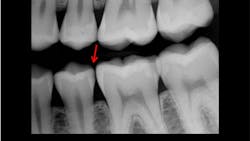

Accuracy of digital radiographic sensors

Experienced dentists, including myself, often compare current digital radiographic images with analog film images of the past. It is easily apparent to the naked eye that analog film shows more detail and accuracy. This deficiency can be problematic relative to identifying initial caries and many other features. Enhancing the digital images helps interpretation of anatomy and restorations but does not satisfy the challenge. Typical general dentists and hygienists make many radiographic images per day. Misinterpretation of images and lack of proper treatment plans and treatment are often the result (figures 1–3).